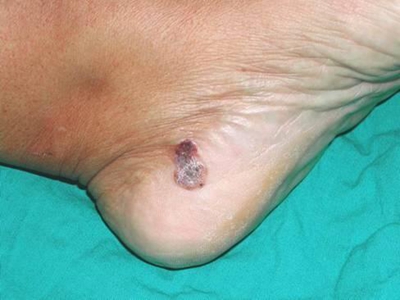

脚后跟

黑斑

恶性雀斑样痣脚后跟上有黑斑图

恶性雀斑样痣发生在脚后跟,表现为黑色的斑块,表面粗糙,伴有溃烂,并有结节、脱皮等症状,为了防止溃烂加重,应遵医嘱尽早采取手术切除治疗。